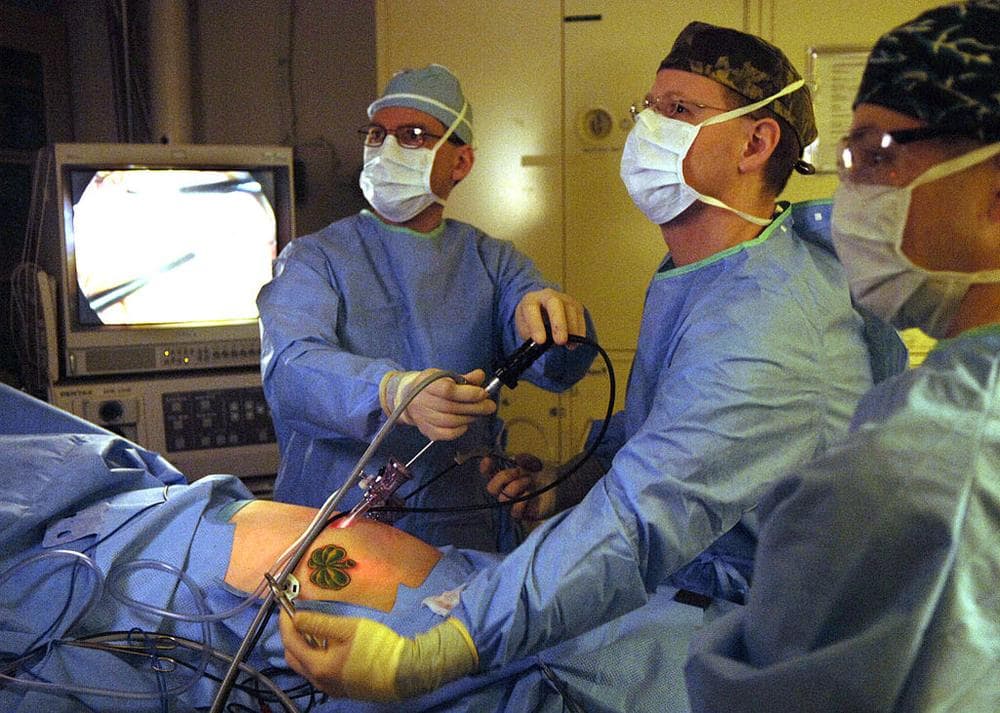

At Dr. Khaled Al-Ruhaimi Hospital, we believe that exceptional care begins with exceptional people. That's why we invest in the most advanced medical technologies and attract highly qualified consultants and specialists across every medical discipline. Our patient‑centered philosophy, combined with a commitment to clinical excellence, ensures that each individual receives world‑class healthcare with compassion and precision.

Our highly experienced team of consultants, specialists and healthcare professionals focus on the root cause of disease to improve the health and well-being of each and every patient. They all have global recognition and accreditations. Our doctors are experts in high-end technology. We provide premium medical care and comfort with modern equipment since our facility is built with the latest advanced technology

Safe and effective surgical procedures for various conditions.